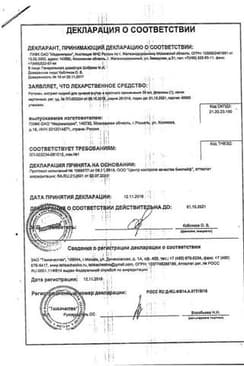

Сертификаты